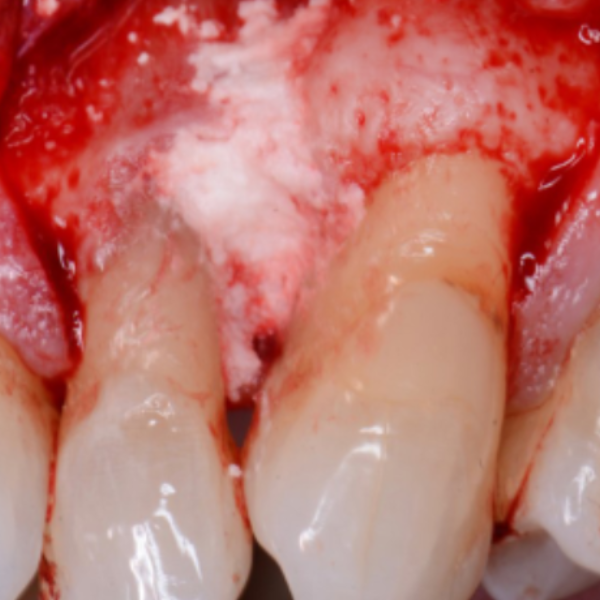

Periodontal Defect Regeneration

Successfully undergone non-surgical periodontal therapy 6mm probing pocket depth on mesial of tooth LR6.